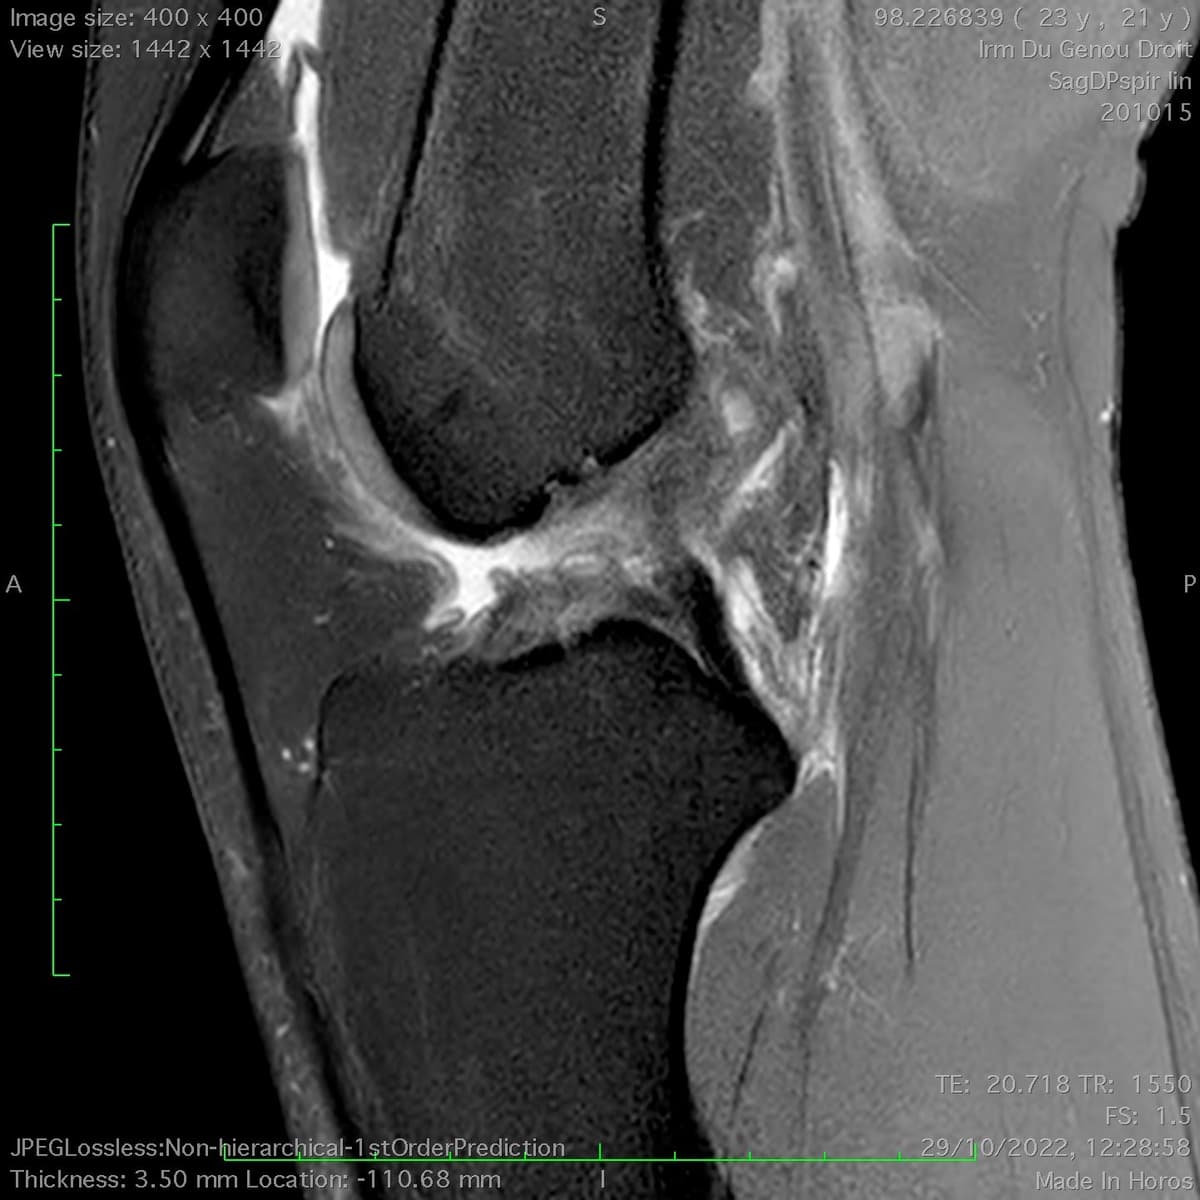

Lésions ménisco-ligamentaires multiples du genou (Triade)

Traumatisme du genou au football sans contact

MRI